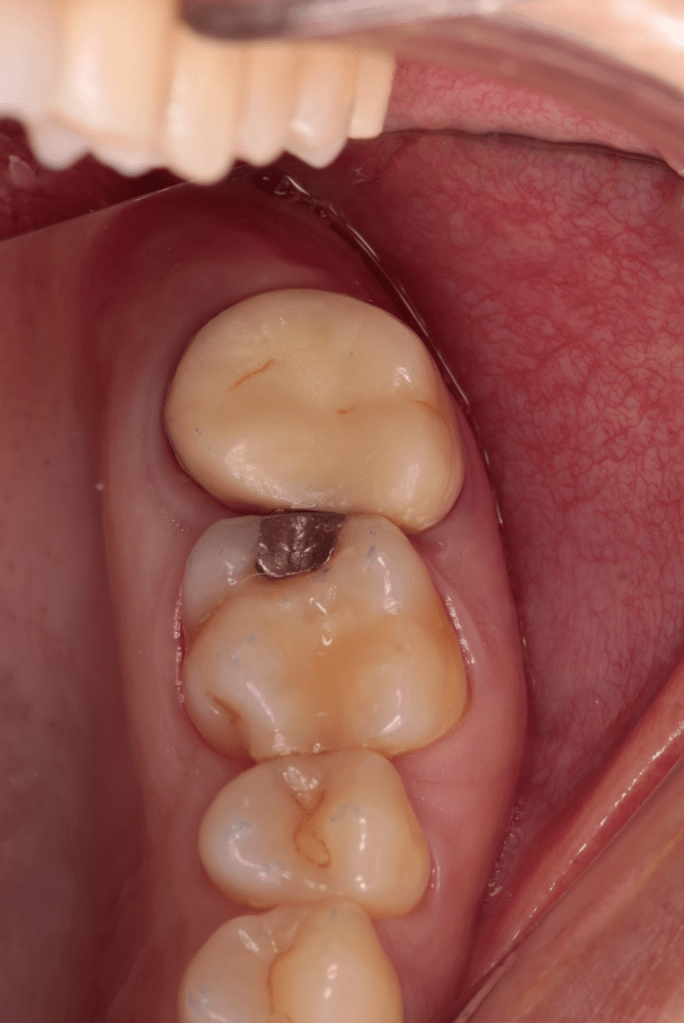

Fisura, remoción amalgama para explorar